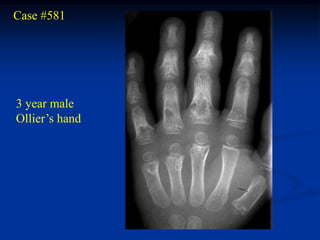

Case #581

3 year male

Ollier’s hand